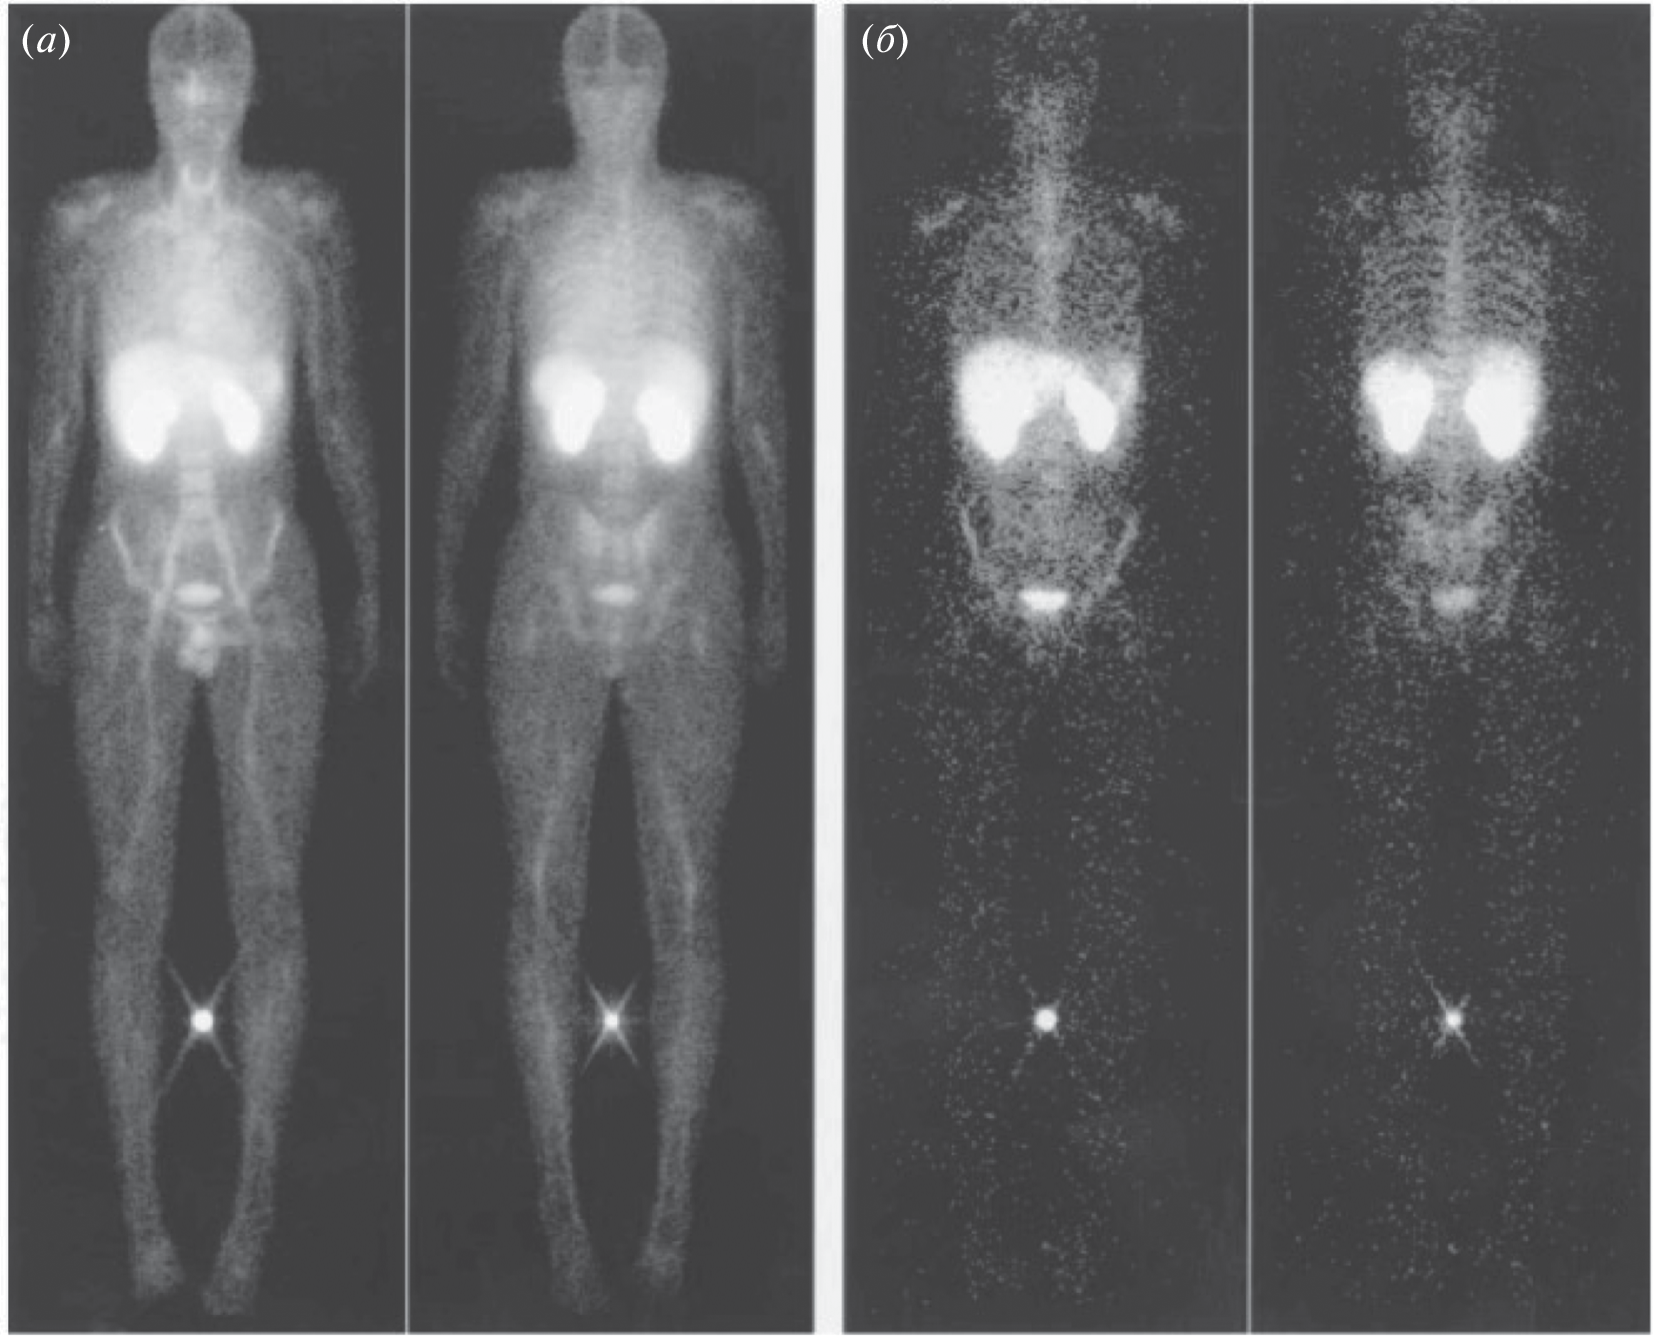

To date, the most common drug for the diagnosis of cancer tumors is [18F]-fluorodeoxyglucose, an radiopharmaceuticals for positron emission tomography diagnostics using the fact of increased glucose metabolism by cancer cells. At the same time, there are a number of cases where an approach based on glucose derivatives is not applicable. In many cases, inflammation or other benign processes are indistinguishable from tumor formations. For such cases of non-specificity of oncologies to glucose (not only tumor cells, but also healthy cells actively consume [18F]-fluorodeoxyglucose), the use of other metabolic pathways is required, which, in the case of a specific tumor in this organ, will be specific to the radiopharmaceuticals used.